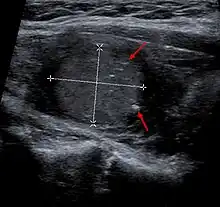

Medullary thyroid carcinoma may also produce a thyroid nodule and enlarged cervical lymph nodes.[4]

Diagnosis is primarily performed via fine needle aspiration of the lesion of the thyroid to distinguish it from other types of thyroid lesions.[6] Microscopic examination will show an amyloid stroma with hyperplasia of parafollicular cells.